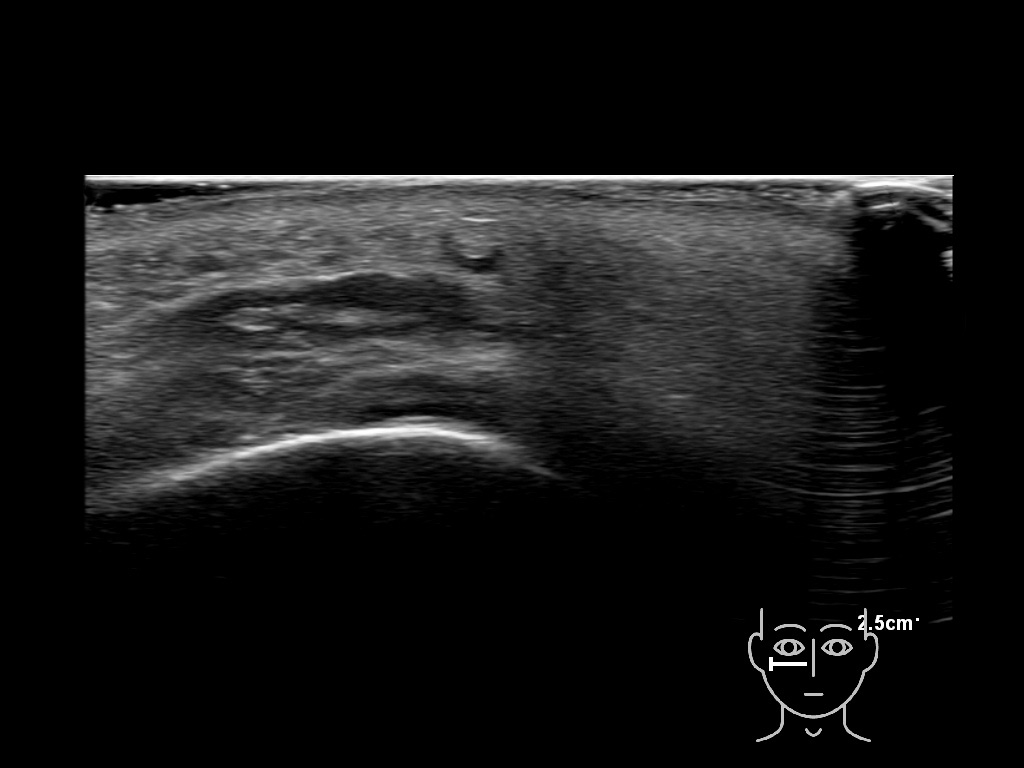

With ultrasound signs of inflammation can be visualized. Edema can be seen as a hyperechoic appearance of the subcutaneous fat, sometimes separated by hypoechoic fluid filled area’s, known as cobblestone appearance. Increased vascularization (hypervascularity) can be seen on colour Doppler. An abscess will appear as a fluid collection appearing as an irregular hypoechoic area with heterogeneous internal echoes and a thickened wall. Posterior acoustic enhancement can be present, and there is vascularity around but not within the mass. Under ultrasound guidance, abscesses can be managed by needle aspirations (18G) under antibiotic cover.

Study the first image to recognize the different layers. If you are sure about the layers, swipe to the second image to view the answer (if applicable).